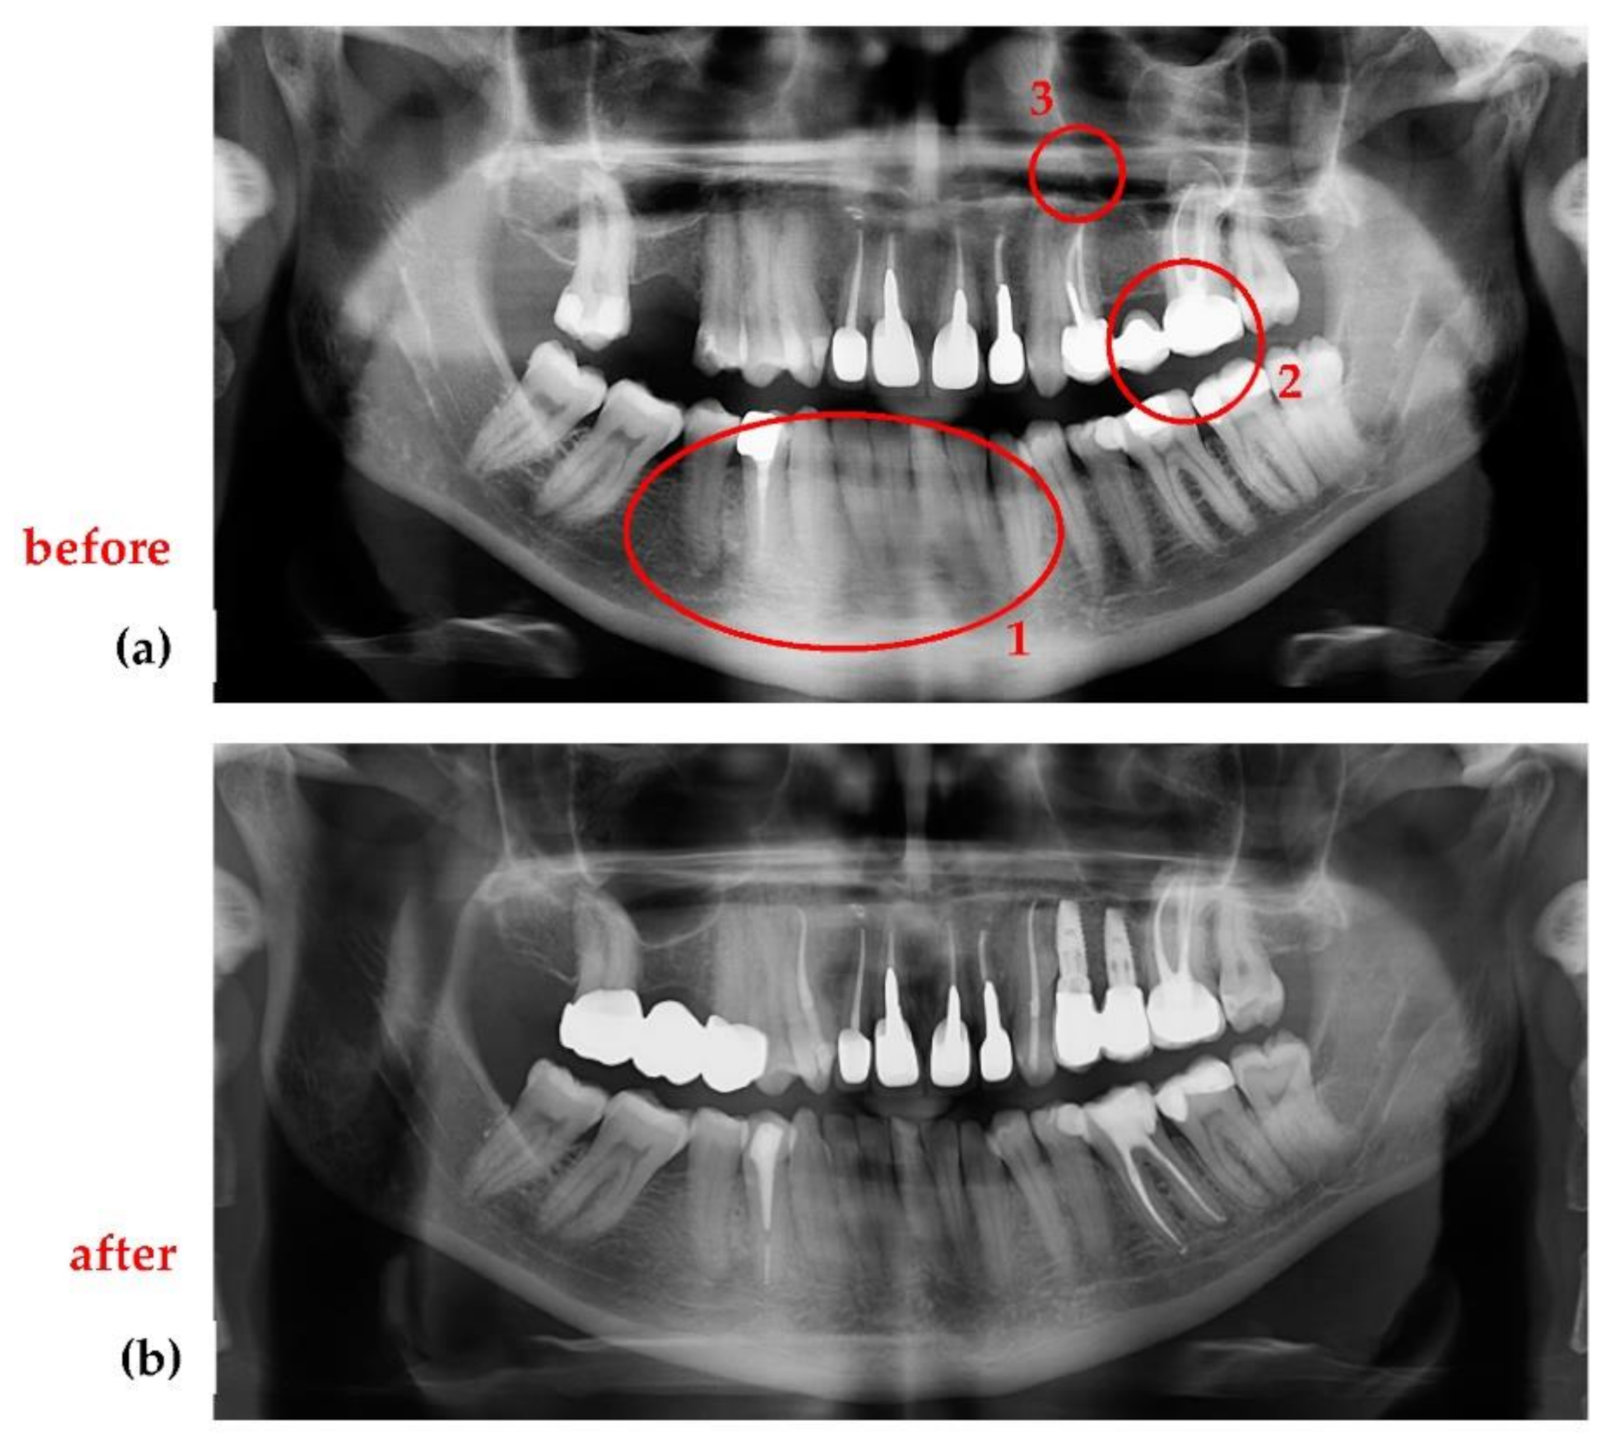

3.3. Application of the Optimization Protocol on Patients (In Vivo)

- Jewelry or any metal around the head or neck must be taken off, otherwise artifacts may appear on radiographs (Figure 17a). This is a general requirement, irrespective of the calibration procedure using OCT. On the other hand, implants and some materials used for dental crowns or dental fillings do not produce artifacts or sparkles around them on radiographs, as shown in the example in Figure 17b. This latter aspect must be considered during calibrations.